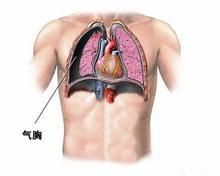

臨床表現

1.突然發生胸痛,呼吸困難,胸悶,嚴重者煩躁不安、大汗、紫紺,呼吸加快,脈搏細速,甚至休克。

2.氣管向健側移位,患側胸部飽滿,呼吸運動減弱或消失,叩診呈鼓音,語顫及呼吸音減弱。

症狀體徵

自發性氣胸 氣胸除外傷或診治用於人工氣胸外,均稱為自發性氣胸。自發性氣胸大多數由於胸膜下氣腫泡破裂引起,也見於胸膜下病灶或空洞潰破、胸膜粘連帶撕裂等原因。胸膜下氣腫泡可為先天性,也可為後天性;前者系先天性彈力纖維發育不良,肺泡壁彈性減退,擴張後形成肺大泡,多見於瘦長型男性,肺部X線檢查無明顯疾病。後者較常見於阻塞性肺氣腫或炎症後纖維病灶的基礎上,細支氣管半阻塞、扭曲,產生活瓣機制而形成氣腫泡,脹大的氣腫泡因營養、循環障礙而退行變性,以致在咳嗽或肺內壓增高時破裂。